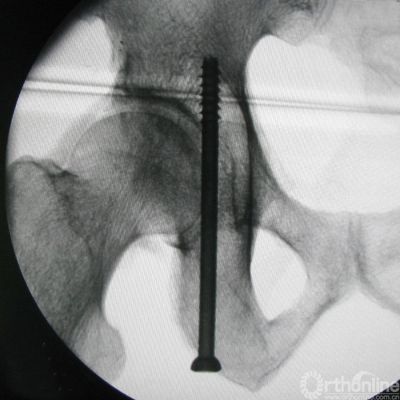

The lag screws were safely inserted into the posterior columns of thepelvic specimens under fluoroscopic control in the iliac oblique view and thetangential views of both the PCPC and medial wall of the acetabulum. During theprocedures, there were no failures in inserting the screws into the properposition. The CT images of the specimens confirmed that the full pathways oflag screws were all in the osseouscorridor of the posterior column. The shortest distance between the posteriorcortex and lag screw was at the level of the greater and lesser sciaticnotches, which was demonstrated on the oblique coronal reconstructed CT images(Figure 6). On the tangential viewsof the PCPC, the greater and lesser sciatic notches also seems closest to thelag screw, which was apparent in the oblique coronal CT images (Figure 4).

Figure 6 The oblique coronalreconstructed CT images shows that the full length of the lag screw is in the boneof the posterior column, and the shortest distance between the posterior cortexand lag screw was at the levels of greater and lesser sciatic notches.